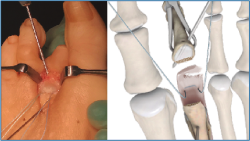

2. Luxamos el dedo a plantar y despegamos cuidadosamente la placa plantar del cuello metatarsal con un periostotomo o un disector de McGlamry (Figura 2).

Figura 2. Movilización cuidadosa de la placa plantar con disector de McGlamry.